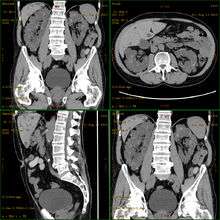

Polycystic kidney disease (PKD or PCKD, also known as polycystic kidney syndrome) is a genetic disorder in which abnormal cysts develop and grow in the kidneys.[1] Cystic disorders can express themselves at any point, infancy, childhood, or adulthood.[2] The disease occurs in humans and some other animals. PKD is characterized by the presence of multiple cysts (hence, "polycystic") typically in both kidneys; however, 17% of cases initially present with observable disease in one kidney, with most cases progressing to bilateral disease in adulthood.[3]